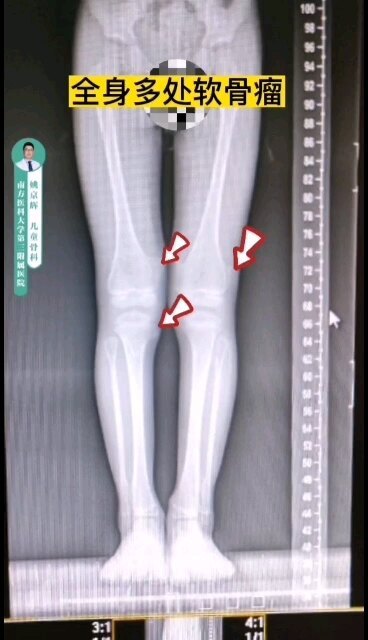

骨軟骨瘤病與內(nèi)生軟骨瘤病簡介臨床上,在所有的良性軟骨系統(tǒng)腫瘤中,以骨軟骨瘤和內(nèi)生軟骨瘤最為常見。骨軟骨瘤和內(nèi)生軟骨瘤多為單發(fā),一旦發(fā)病部位達(dá)到兩處及以上,即可相應(yīng)診斷為骨軟骨瘤病和內(nèi)生軟骨瘤病。這是兩種罕見但重要的骨骼疾病,對病人的生活質(zhì)量和健康狀態(tài)有著顯著的影響,往往在兒童及青少年時(shí)期由于骨骼畸形及生長障礙就醫(yī)而被診斷。成年后,由于關(guān)節(jié)對位不良,常常導(dǎo)致關(guān)節(jié)疼痛和退行性變。更為重要的是,盡管兩者為良性病變,但均具有惡變?yōu)檐浌侨饬龅娘L(fēng)險(xiǎn)。因此,本文將重點(diǎn)介紹這兩類疾病的病因、癥狀、主要治療方法,以及預(yù)防疾病惡變需要注意些什么,供大家學(xué)習(xí)交流。一、骨軟骨瘤病骨軟骨瘤?。ǘ喟l(fā)骨軟骨瘤),又被稱為遺傳性多發(fā)性外生骨疣(MultipleHereditaryExostoses,MHE),是一種常染色體顯性遺傳病。它主要表現(xiàn)為多個(gè)外生骨疣(即骨軟骨瘤)在骨骼表面背向關(guān)節(jié)生長,這些外生骨疣可以在全身各處出現(xiàn),但尤其常見于長骨的干骺端,如股骨、脛骨和肱骨,也常見于中軸骨,如骨盆、肩胛骨和脊柱。1.遺傳特點(diǎn)骨軟骨瘤病的發(fā)生與EXT1或EXT2基因的突變有關(guān),約70-94%的多發(fā)骨軟骨瘤病患者存在EXT1/2胚系突變。EXT1基因在染色體8q24區(qū)域,EXT2基因位點(diǎn)在11p11-13,骨軟骨瘤病以EXT1突變更為常見。EXT基因編碼的蛋白質(zhì)Exostosin參與了細(xì)胞表面的分子信號傳導(dǎo),包括對多種生長因子的組織分布及生物有效性的調(diào)節(jié)。當(dāng)EXT1或EXT2基因突變時(shí),會影響軟骨細(xì)胞的信號傳導(dǎo),導(dǎo)致軟骨細(xì)胞過度增殖和骨骼發(fā)育異常。骨軟骨瘤病作為顯性遺傳病,意味著只要父母中有一方攜帶這種突變基因,子女就有同等幾率患病。兩個(gè)顯著的特點(diǎn)為,(一)、男性患者由于青春期長,生長板閉合較晚,因此一般男性畸形程度較女性重。(二)、EXT1基因突變的患者表型特征更突出,無論男女,身體骨軟骨瘤的數(shù)量、肢體的短縮程度、身材矮小程度和中軸骨受累的幾率都比EXT2基因突變更為明顯(p<0.0005)(JBoneJointSurgAm,2011;ClinOrthopRelatedRes,2015)。2.臨床表現(xiàn)骨軟骨瘤病通常在兒童時(shí)期發(fā)病,隨著骨骼的生長,外生骨疣的數(shù)量和大小會逐漸增加?;颊咧饕Y狀包括:1)骨骼畸形和身材矮小:骨軟骨瘤會導(dǎo)致骨骼生長異常和畸形,從而影響身高。2)疼痛和功能障礙:骨軟骨瘤可能會壓迫周圍的肌肉、肌腱、神經(jīng)和血管,導(dǎo)致疼痛和功能障礙。3)關(guān)節(jié)活動受限:骨軟骨瘤會影響關(guān)節(jié)活動,導(dǎo)致關(guān)節(jié)活動受限。4)惡變風(fēng)險(xiǎn):雖然骨軟骨瘤病是良性疾病,但仍有惡變?yōu)檐浌侨饬龅娘L(fēng)險(xiǎn),這種惡變通常發(fā)生在成年患者身上,惡變率為5%左右。意大利Rizzoli研究中心研究了多發(fā)性骨軟骨瘤的基因型-表型的相關(guān)性,調(diào)查了529名患者,將患者分為輕、中和重三型(如下表),26例惡變患者多發(fā)骨軟骨瘤的診斷年齡平均為7.6歲,惡變診斷年齡平均為28.6歲。惡變?yōu)檐浌侨饬龅牟课蛔疃嘁娪诠桥韬图珉喂牵窗l(fā)現(xiàn)惡變的風(fēng)險(xiǎn)與性別、畸形程度、骨軟骨瘤的數(shù)量以及EXT1/2突變顯著相關(guān)(JBoneJointSurgAm,2011)。3、臨床分型臨床上按照患者表型特征分為輕(I型),中(II型)和重(III型)三型。529患者中1/4為重型,其他3/4為輕中型(輕/中型約1:1)。(來自JBoneJointSurgAm,2011)典型病例男性,29歲,自幼診斷為多發(fā)骨軟骨瘤,因骨盆部位包塊入院,術(shù)前檢查懷疑骨盆骨軟骨瘤惡變,手術(shù)行腫瘤切除,保留髖關(guān)節(jié)后柱,股骨頭髖臼重建,假體置換,術(shù)后病理確診軟骨肉瘤I級,現(xiàn)為術(shù)后10年,腫瘤未復(fù)發(fā),功能良好。隨訪10年行走視頻二、內(nèi)生軟骨瘤病內(nèi)生軟骨瘤?。ǘ喟l(fā)內(nèi)生軟骨瘤,Enchondromatosis)是一種非遺傳性基因突變導(dǎo)致的疾病,主要特征為骨內(nèi)多處出現(xiàn)內(nèi)生軟骨瘤。這些軟骨瘤通常是良性的,但在某些情況下可以惡變?yōu)檐浌侨饬?。Ollier病和Maffucci綜合征是內(nèi)生軟骨瘤病最常見的兩種類型。Ollier?。阂远喟l(fā)性內(nèi)生軟骨瘤為特征,通常累及長骨和扁平骨,如股骨、脛骨、骨盆等。患者可能在兒童時(shí)期就表現(xiàn)出癥狀,隨著骨骼成熟,軟骨瘤的數(shù)量和大小可能會增加。Ollier病患者除了骨骼畸形外,還可能面臨骨折和疼痛的風(fēng)險(xiǎn)。Maffucci綜合征:即軟骨營養(yǎng)障礙-血管瘤綜合征,是一種更為罕見的內(nèi)生軟骨瘤病,其特點(diǎn)是多發(fā)性內(nèi)生軟骨瘤與多發(fā)性軟組織血管瘤同時(shí)存在。血管瘤通常位于上肢,如手部和前臂,但也可能出現(xiàn)在下肢和軀干。Maffucci綜合征患者除了骨骼畸形外,還可能面臨血管瘤破裂出血和內(nèi)生軟骨瘤惡變?yōu)檐浌侨饬龅娘L(fēng)險(xiǎn)。女性,63歲,Maffucci綜合征,骨盆及股骨近遠(yuǎn)端受累,股骨畸形。左側(cè)骨盆內(nèi)生軟骨瘤惡變?yōu)檐浌侨饬觥?.遺傳特點(diǎn)內(nèi)生軟骨瘤病的病因尚未完全明確,但研究表明,非遺傳性基因突變起著重要作用。IDH1基因位于染色體2q33.3,IDH2基因在15q26.1,IDH基因編碼一種酶稱為異檸檬酸脫氫酶,這種酶在細(xì)胞內(nèi)催化異檸檬酸轉(zhuǎn)化為α-酮戊二酸。IDH1/2突變見于81%Ollier病和77%Maffucci綜合征患者。IDH1突變常見的類型是在IDH1基因的第132位氨基酸發(fā)生突變,替換了精氨酸(arginine,R)為組氨酸(histidine,H),因此被稱為R132H突變。IDH2基因突變發(fā)生在第四外顯子的R140和R172。IDH1/2突變導(dǎo)致酶活性的異常改變,使其催化產(chǎn)物從α-酮戊二酸轉(zhuǎn)變?yōu)?-羥戊二酸(2-hydroxyglutarate,2-HG),細(xì)胞內(nèi)促癌代謝產(chǎn)物2-HG異常積累,影響骨骼發(fā)育,導(dǎo)致內(nèi)生軟骨瘤的形成。需要強(qiáng)調(diào)的是,內(nèi)生軟骨瘤病并非遺傳性疾病,因此患者的家族成員通常不會患病。2.臨床表現(xiàn)內(nèi)生軟骨瘤病早期通常不伴明顯癥狀,隨著骨骼的生長,內(nèi)生軟骨瘤的數(shù)量和大小也會逐漸增加?;颊呖赡艹霈F(xiàn)骨骼畸形、關(guān)節(jié)活動受限等癥狀。在嚴(yán)重病例中,軟骨瘤可能累及整個(gè)骨骼系統(tǒng),導(dǎo)致嚴(yán)重的殘疾。此外,與骨軟骨瘤病類似,內(nèi)生軟骨瘤病也存在惡變?yōu)檐浌侨饬龅娘L(fēng)險(xiǎn)。惡變率因病情嚴(yán)重程度而異,但總體上高于骨軟骨瘤病,其中在Maffucci綜合征患者中,惡變率甚至高達(dá)50%以上。因此,內(nèi)生軟骨瘤病患者同樣需要定期復(fù)查。三、治療方法與管理策略目前,對于骨軟骨瘤病和內(nèi)生軟骨瘤病尚無有效的藥物治療方法。對于無癥狀或癥狀輕微的患者,通常無需治療,只需定期隨訪觀察。然而,當(dāng)骨疣或內(nèi)生軟骨瘤壓迫周圍組織、引起疼痛或關(guān)節(jié)活動受限時(shí),手術(shù)治療是可供選擇的手段,手術(shù)方法包括切除骨疣、矯正畸形等。對于成年患者和惡變風(fēng)險(xiǎn)較高的患者,定期復(fù)查尤為重要。通過X線、CT和MRI等影像學(xué)檢查手段,可以及時(shí)發(fā)現(xiàn)并處理惡變病灶。四、骨軟骨瘤病和內(nèi)生軟骨瘤病的異同五、總結(jié)與展望因此回到本文的標(biāo)題上,骨軟骨瘤病是遺傳性疾病,而內(nèi)生軟骨瘤病是非遺傳性疾病。二者均是罕見的骨骼疾病,雖然它們是良性的,但仍有惡變?yōu)檐浌侨饬龅娘L(fēng)險(xiǎn)。定期隨訪和及時(shí)治療可以幫助預(yù)防惡性變,改善患者的預(yù)后。